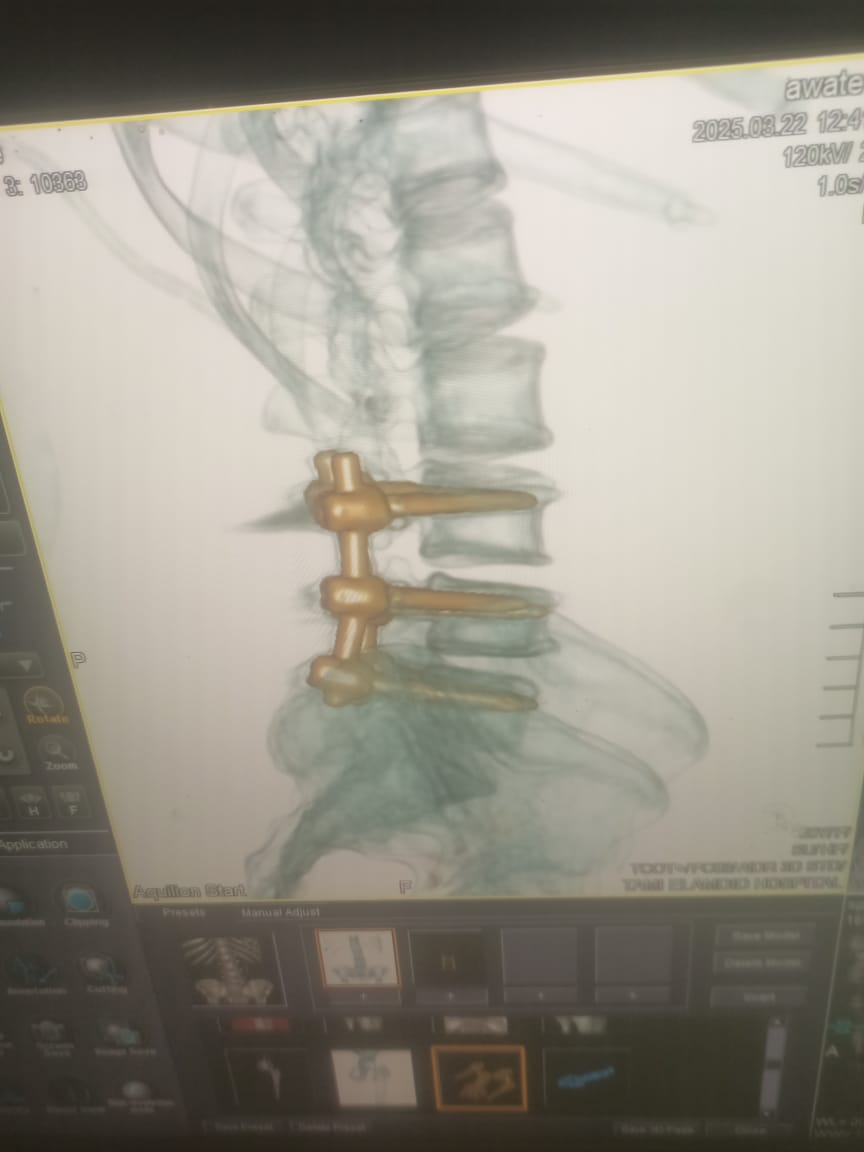

وأضاف وكيل الوزارة بأن المريضة تبلغ من العمر 45 عاما، وقد حضرت إلى المستشفى وهى تعانى من سقوط فى القدم، وصعوبة شديدة في الحركة، وعدم تحكم فى البول، بالإضافة إلى آلام شديدة فى الظهر، وعقب إجراء الفحوصات اللازمة تبين وجود 2 غضروف قطنى أحدهما منفجر بين الفقرات القطنية الثالثة والرابعة والخامسة، وبناء عليه احتاجت المريضة إلى تدخل طارئ تم على إثره استئصال الغضروفين، وتثبيت الفقرات القطنية بواسطة 6 مسامير، وشريحتين، وتوسيع القناة العصبية.

فيما أكد الدكتور أحمد البيلى، وكيل المديرية للطب العلاجى على أن حالة المريضة مستقرة مع ملاحظة تحسن فى سقوط القدم، وتحكم فى البول، مشيراً إلى أن العملية تأتى فى إطار حرص صحة الدقهلية على التوسع في تقديم الخدمات الطبية المتخصصة، ورفع إمكانيات وقدرات المستشفيات العامة والمركزية والنوعية.